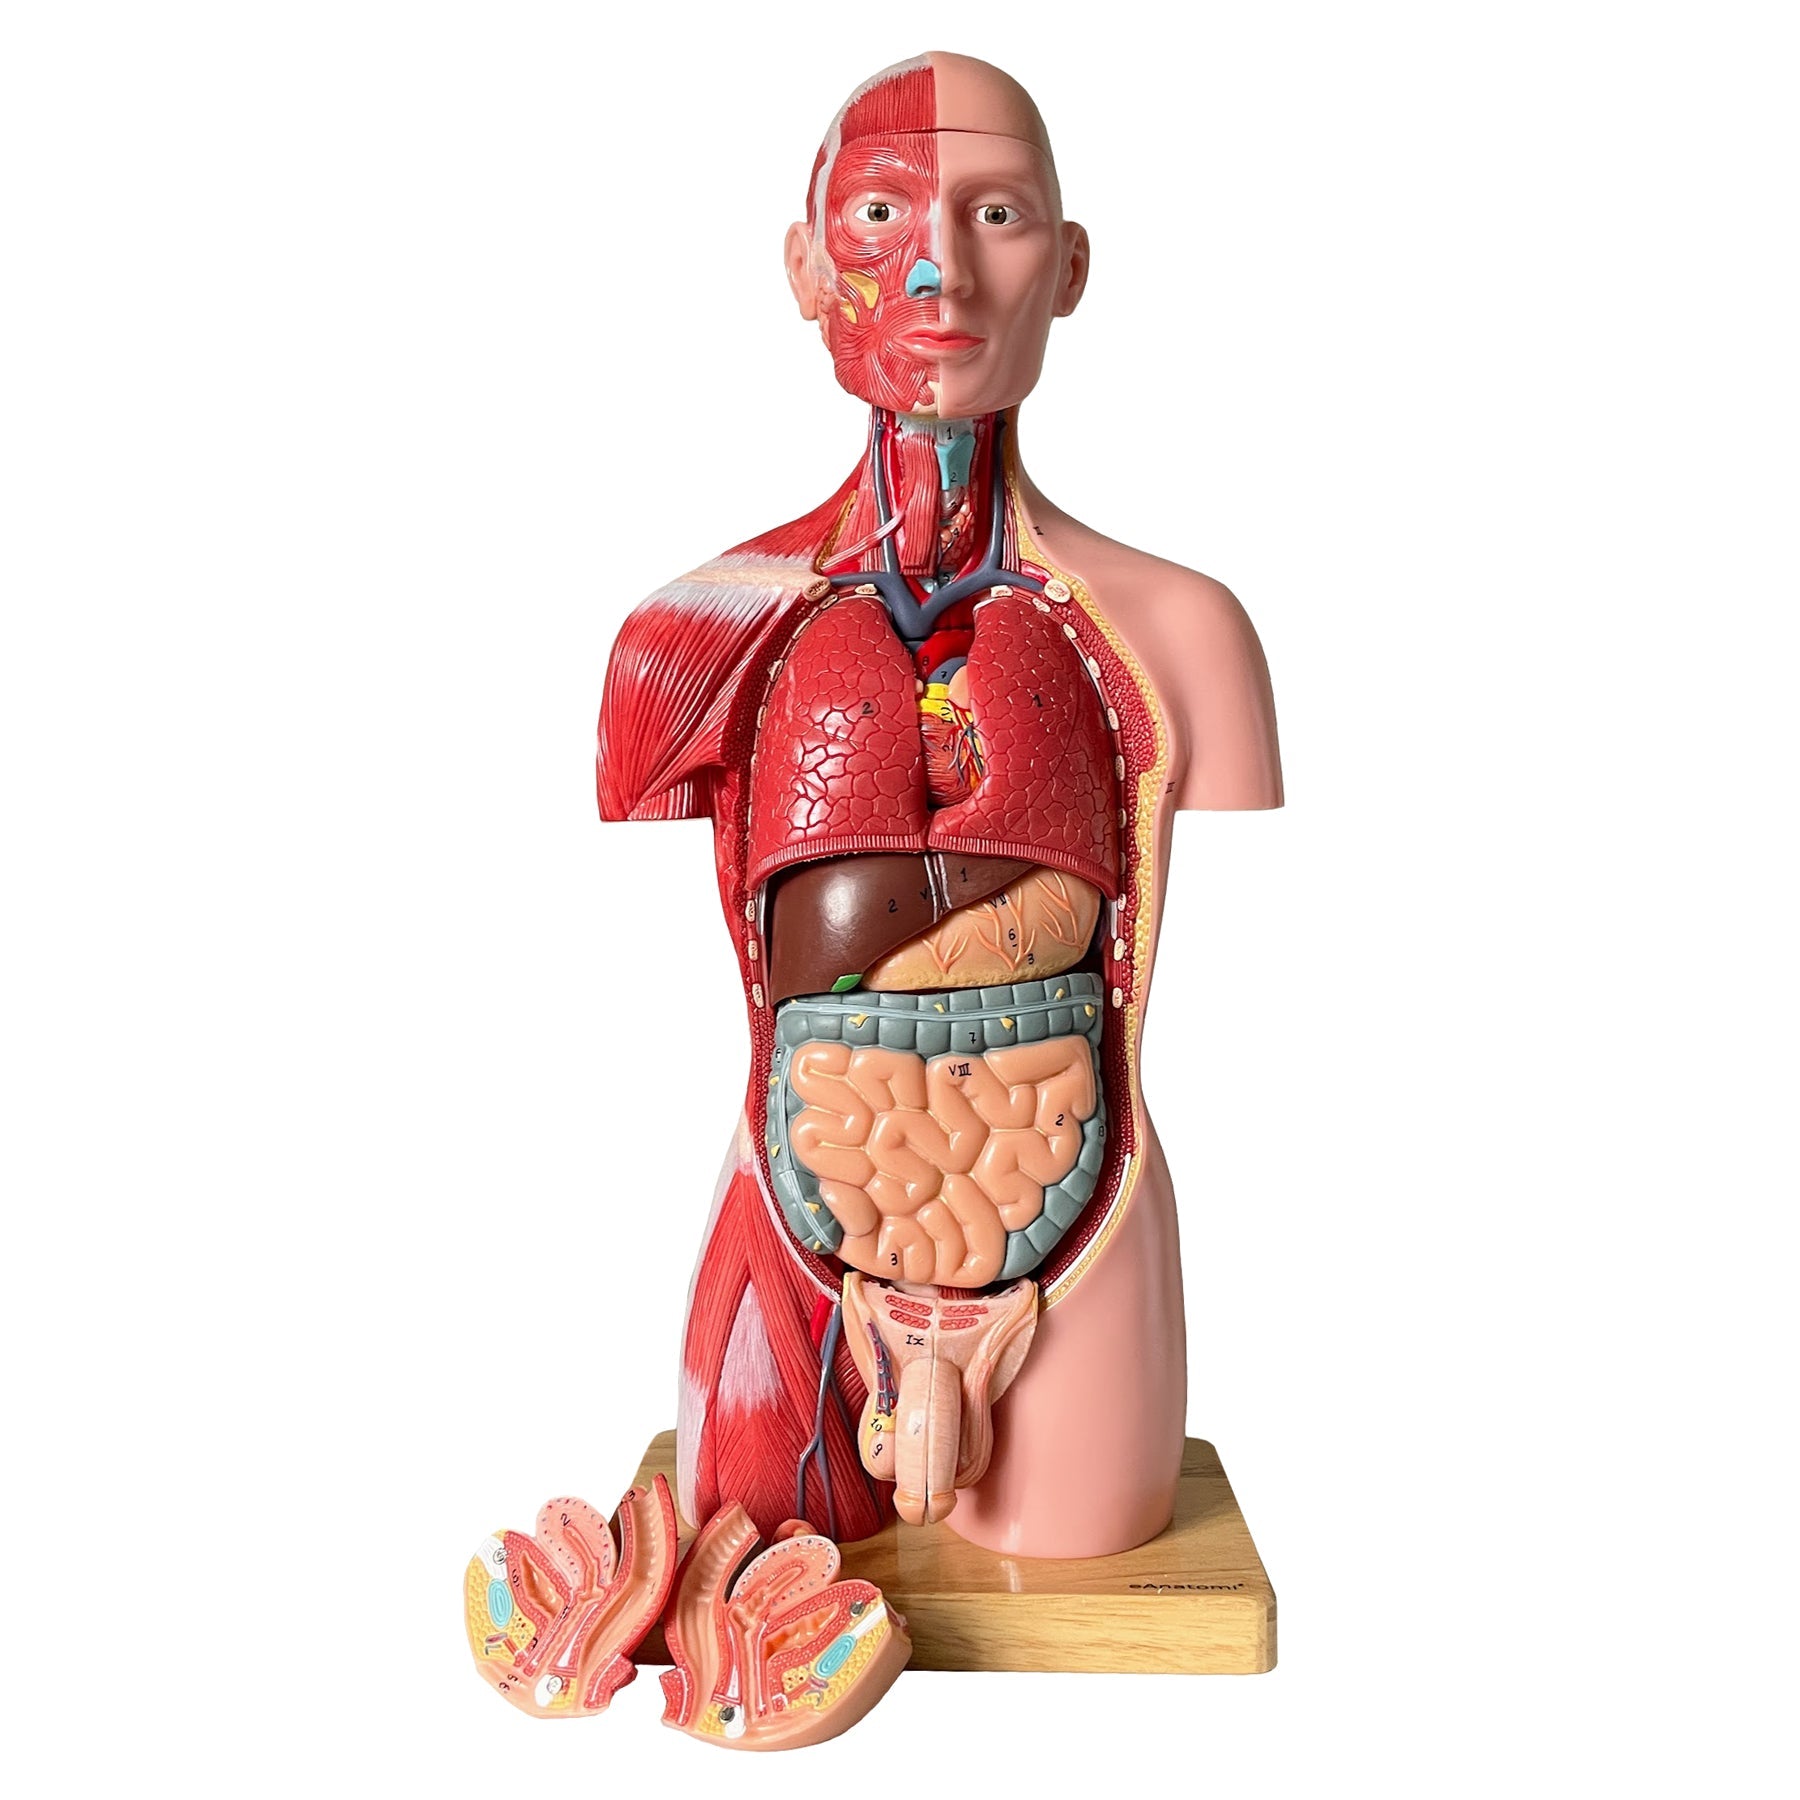

Denna skallmodell erbjuder den mest verklighetstrogna benstrukturen, den mest exakta återgivningen av de anatomiska detaljerna och känslan av att röra vid äkta ben. Dessutom är benfärgen något gulaktig, vilket gör att skallmodellen framstår som mer realistisk. Den är tillverkad i SOMSO-plast av tillverkaren SOMSO, som är världskänd för mycket hög kvalitet. Modellen används bland annat inom läkarutbildningen i Danmark.

Modellen är gjuten i en storlek som motsvarar en vuxen person. Längden är 17,5 cm och bredden 14,1 cm. Den väger cirka 800 gram. Skalkepsen ("toppen") kan tas av, så bl.a. skallbasen (basis cranii interna) kan studeras. Skalkepsen hålls på plats via praktiska metallkrokar och små plastnålar (plaststiften syns bara när locket tas bort). Hela vägen runt skallen framstår monteringen jämn och diskret när kaloten är påsatt (se bilderna till vänster).

Mandibeln är fäst med en fjäder. Den kan enkelt och snabbt demonteras. Skallemodellen kan alltså delas upp i 3 delar.